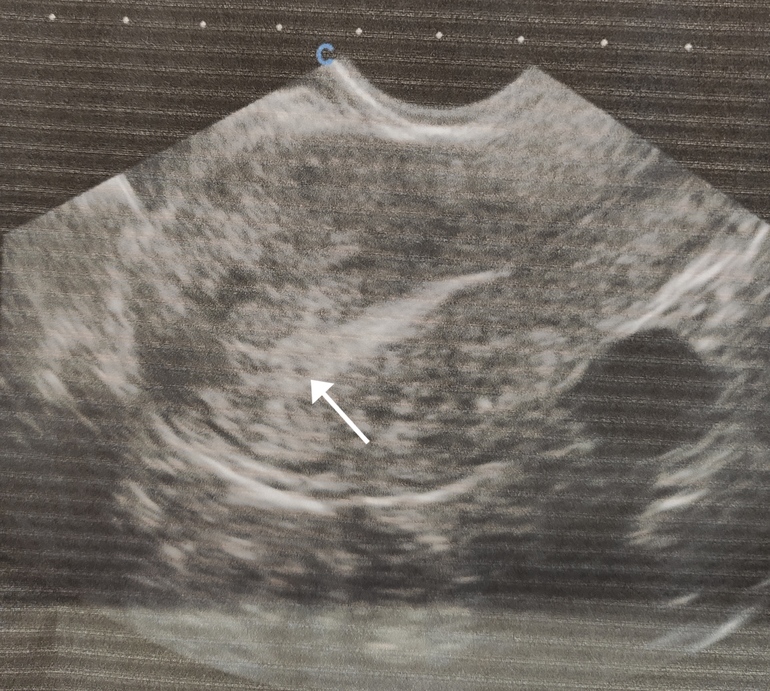

Гляделки. Есть полосочка? (Категория для тех, кто незнает свой ДПО)Сегодня ходила на УЗИ врач ничего не увидел т.к. срок маленький, но в матке вроде похожее на яйцо

. Затем сдала кровь на ХГЧ, ответ завтра. Жду. Ну и сегодняшние тесты